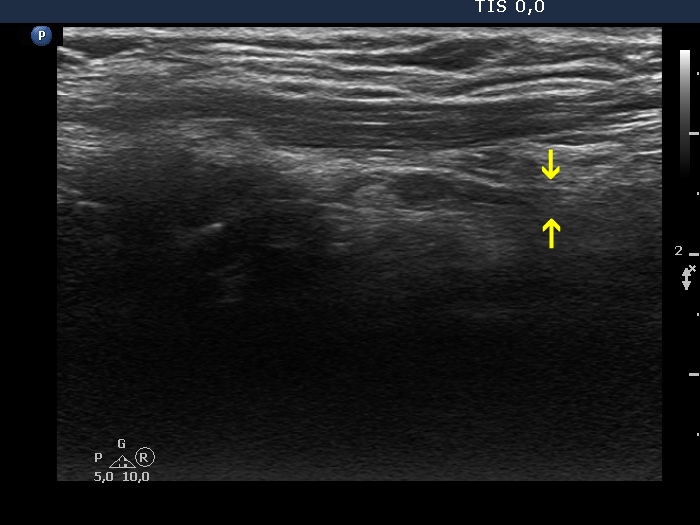

The operated thyroid - case 337 (ultrasonographic picture 6b)

Left lobe, longitudinal scan. The hypoechoic mass has upper and lower (yellow arrows) tails which means that this does not correspond to thyroid tissue but to muscle fiber.